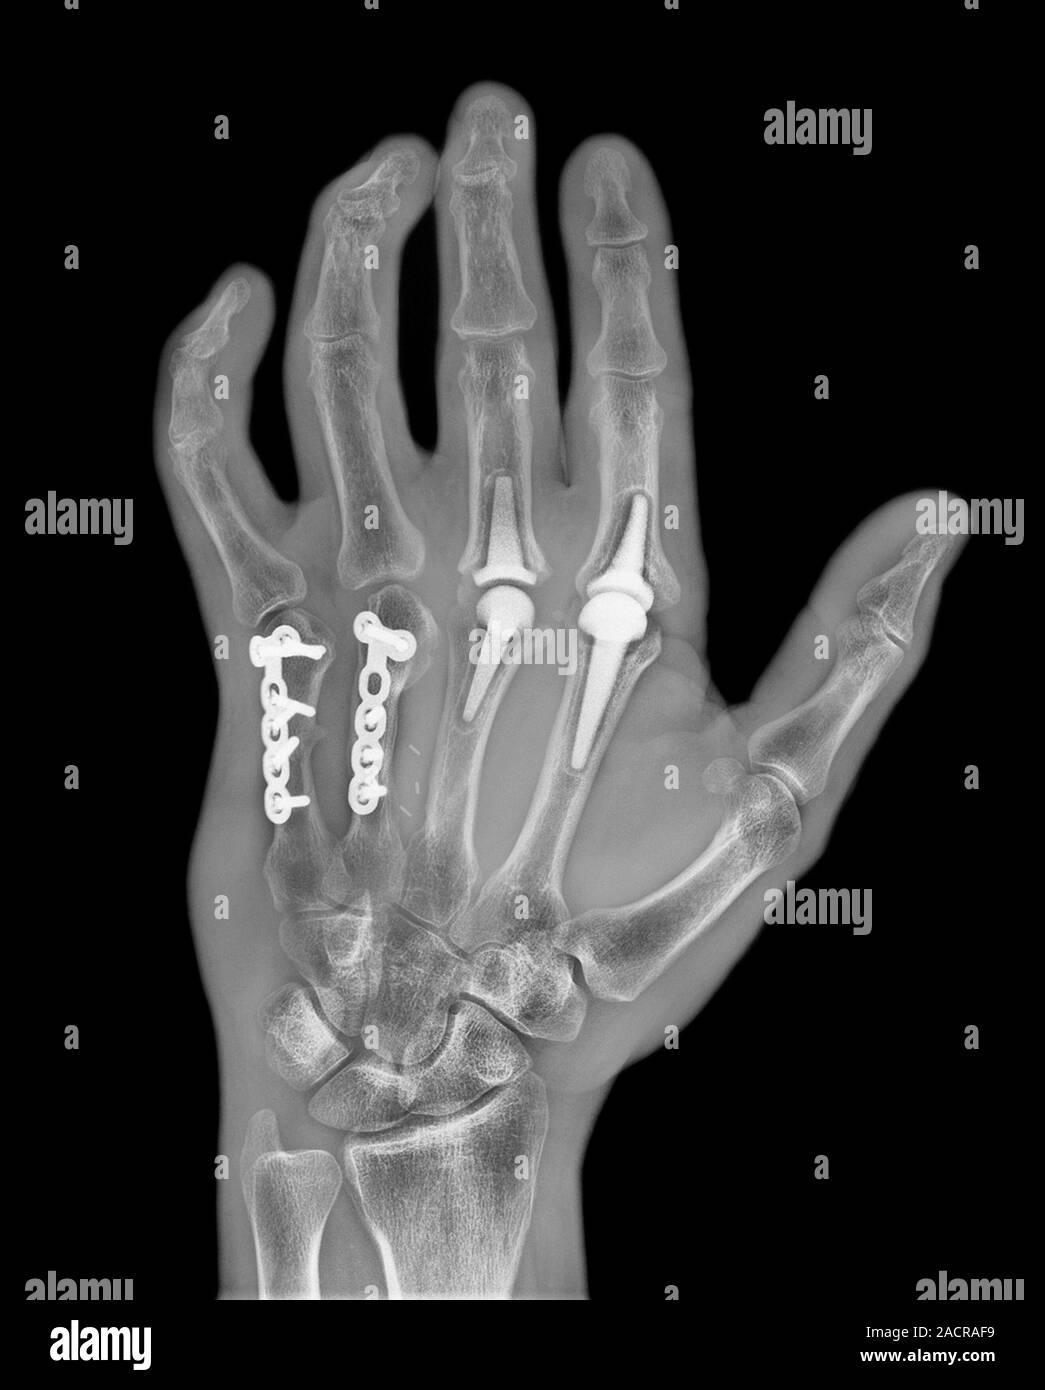

From www.alamy.com

Knuckle replacement. Xray of the hand of a 41 year old male patient Can Knuckle Joints Be Replaced Learn about the two main surgical options for hand arthritis: Find out how they are used for different joints, what are the pros and cons, and what are the possible complications. Fusion and total knuckle replacement. Finger joint replacements are most frequently performed to treat arthritis; An mcp joint replacement is most commonly performed when your knuckle joint is painful,. Can Knuckle Joints Be Replaced.

Knuckle replacement. Xray of the hand of a 41 year old male patient Can Knuckle Joints Be Replaced Learn about the two main surgical options for hand arthritis: Learn about the surgical procedure to replace the arthritic knuckle joints of your hand with silicone implants or spacers. An mcp joint replacement is most commonly performed when your knuckle joint is painful, stiff or cannot move because of arthritis or injury. Arthritis can affect the knuckles of your fingers. Can Knuckle Joints Be Replaced.